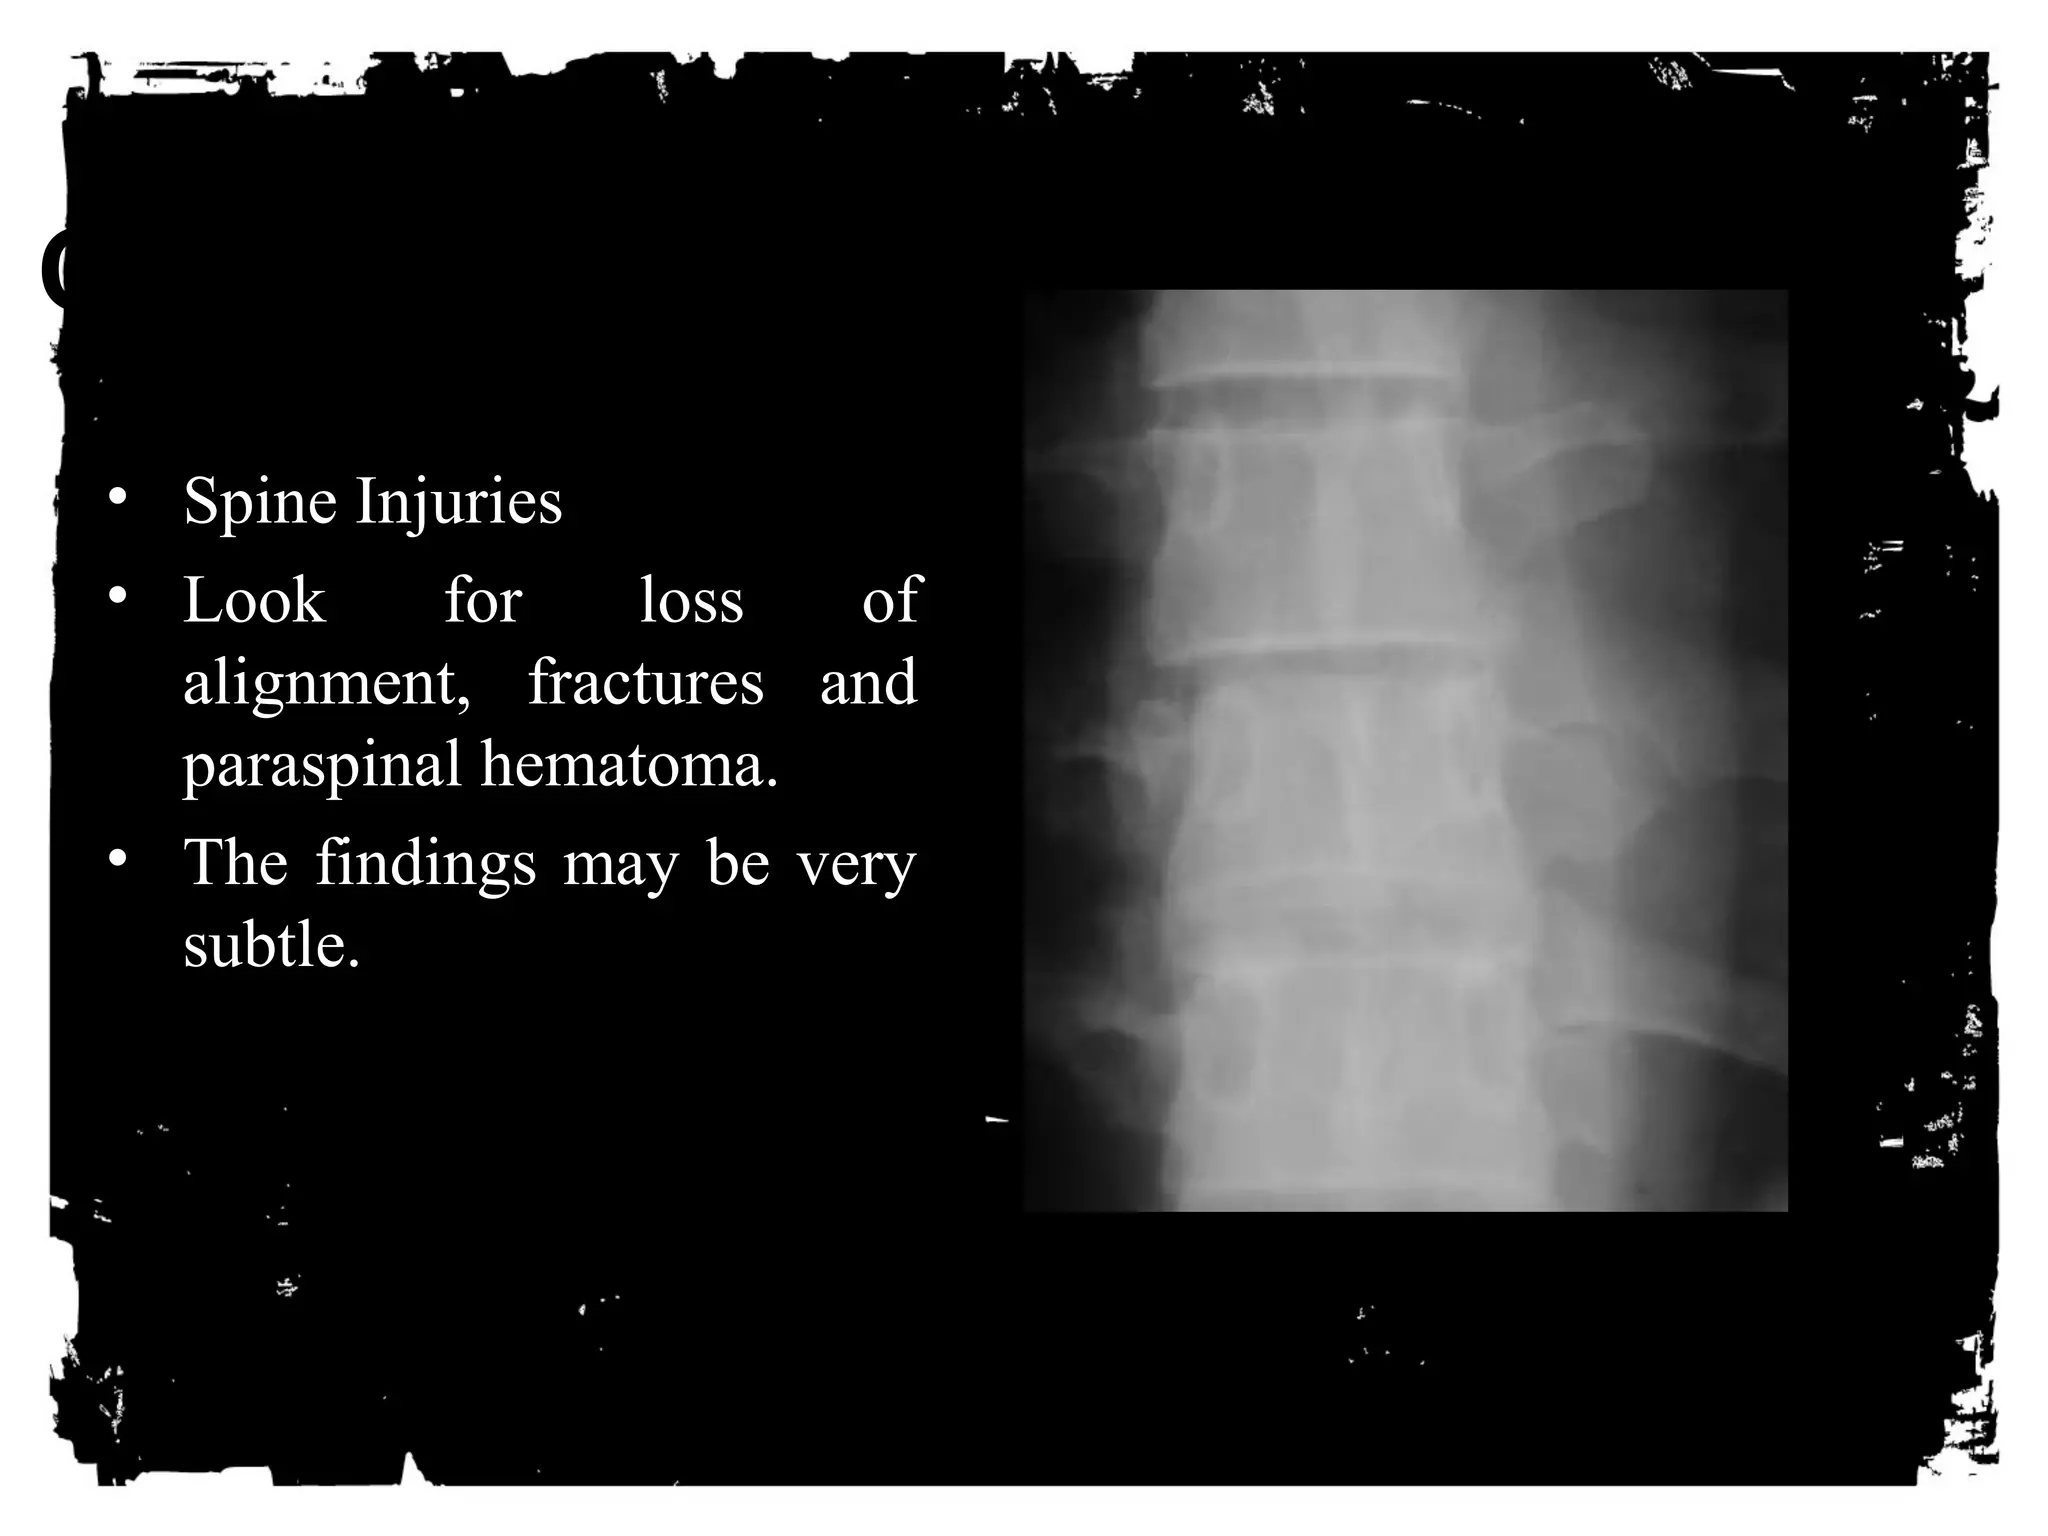

• Spine Injuries

• Look for loss of

alignment, fractures and

paraspinal hematoma.

• The findings may be very

subtle.

• CT is the imaging

modality of choice for

evaluation of these

injuries.